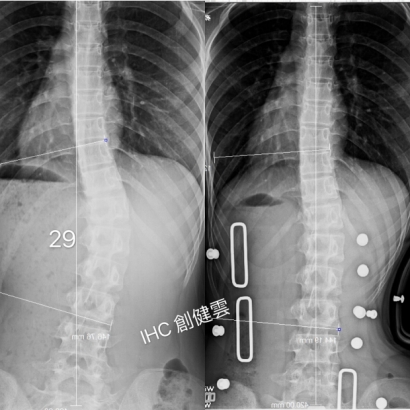

14歲脊椎側彎男生,腰彎29度